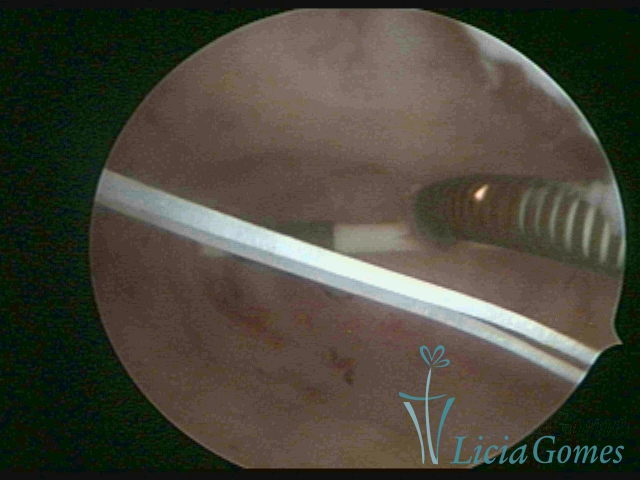

Myometrium punctured IUD